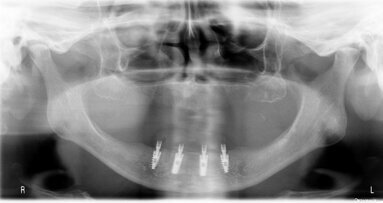

Autorzy przedstawiają obserwacje dotyczące okołowszczepowych zmian zapalnych występujących po leczeniu implantologicznym w okresie 4 lat. Obserwowano 3...